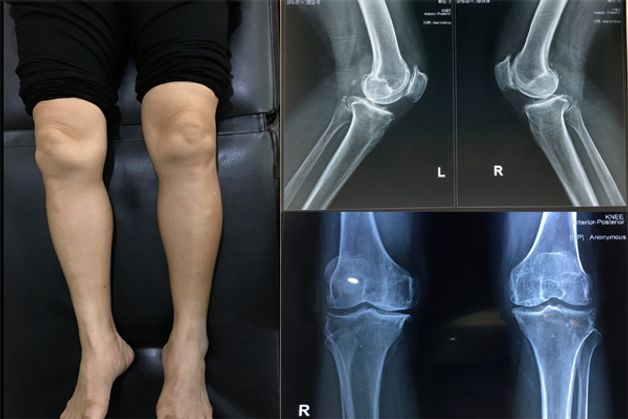

Khớp gối là cơ quan quan trọng, chịu trách nhiệm gánh vác toàn bộ gánh nặng trọng lượng cơ thể. Đây cũng là khớp vận động nhiều nhất nên khớp gối rất dễ bị thoái hóa. Thoái hóa khớp gối là tình trạng sụn khớp ở đầu gối bị bào mòn, trở nên xù xì và mỏng, mất đi tính đàn hồi; từ đó gây cản trở vận động, khó khăn khi đi lại cho người bệnh.

Tuổi tác cao là một trong những nguyên nhân chính gây bệnh thoái hóa khớp gối

– Teo khớp gối: Đây là biểu hiện nghiêm trọng do sụn khớp đã bị tổn thương nặng.